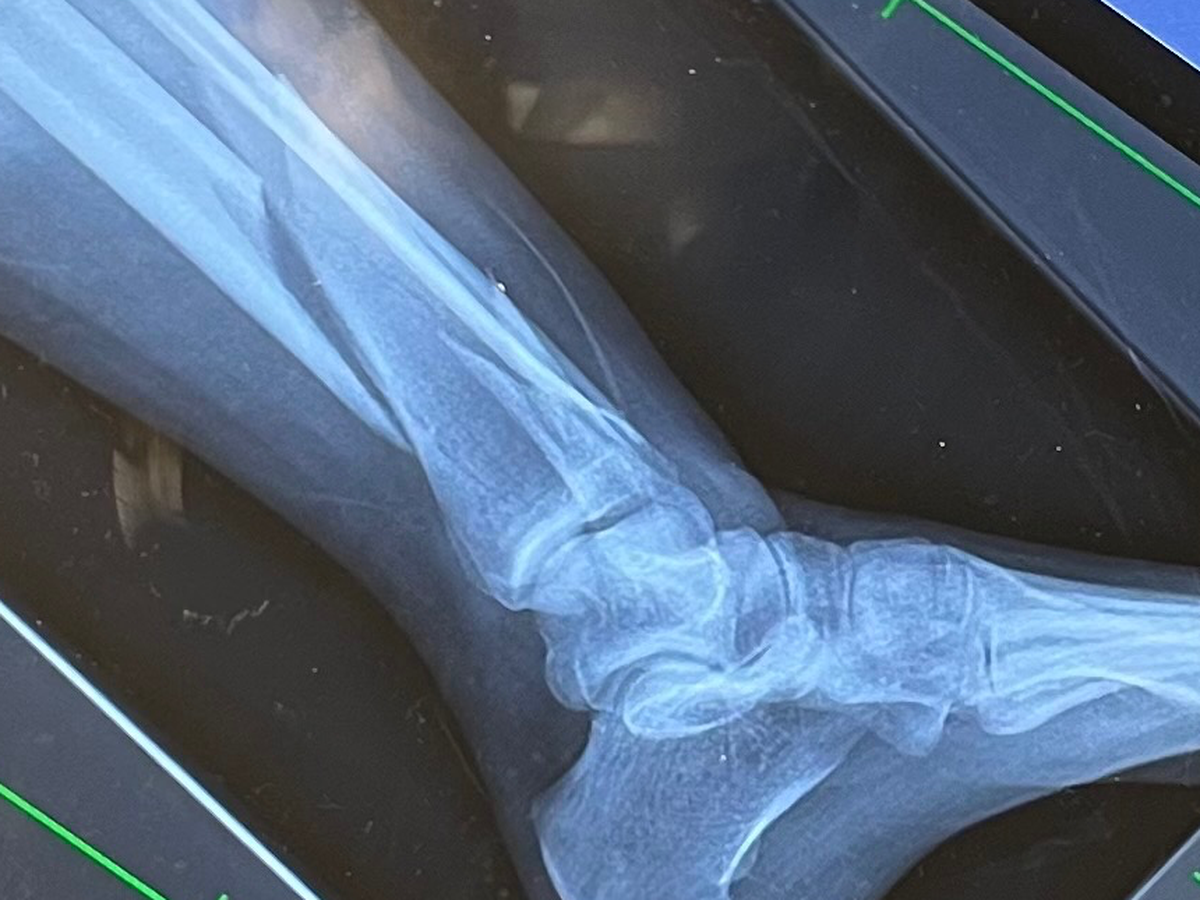

I was rushed to the ER. My partner en route, surrounded by strangers and in pain, I was out of my depth. After an X-ray and some morphine, I was told three things: that both bones in my left leg were broken, that my pain made sense, and that I would need to have surgery.

They sedated me, repositioned my floating bones, and put them in a temporary cast till my surgery. It hurt to move.